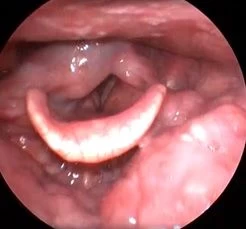

Клинический случай №3. Коагуляция расширенного сосуда правой голосовой складки с применением лазера с длиной волны 445 нм.

Восстановление нормальной слизистой оболочки произошло быстро, без признаков воспалительных процессов.

Рис 3А. Расширенный сосуд средней треть правой голосовой складки. Перед операцией.

Рис 3Б. Расширенный сосуд средней треть правой голосовой складки. На 10 день после операции.